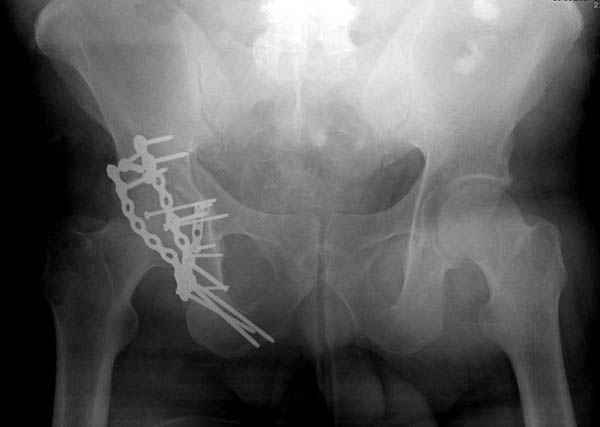

Дополнительно имеется перелом ацетабулума: задняя

колонна с полупоперечным переломом, и переломы костей лица.

На седьмой день зафиксирован перелом ацетабулума через задний доступ. Перед операцией для профилактики DVT, IVC фильтер, также получает Lovenox.

Там множество обычных 2.7 мм шурупов, потом идет фиксация основными пластинами.